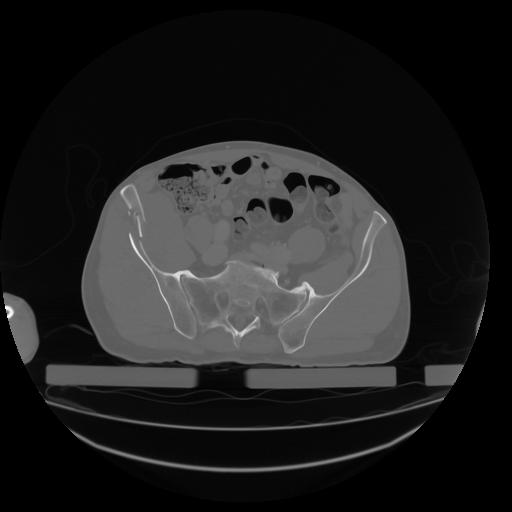

27 CUERPO,CE,Axial,3.0,CUERPO,,